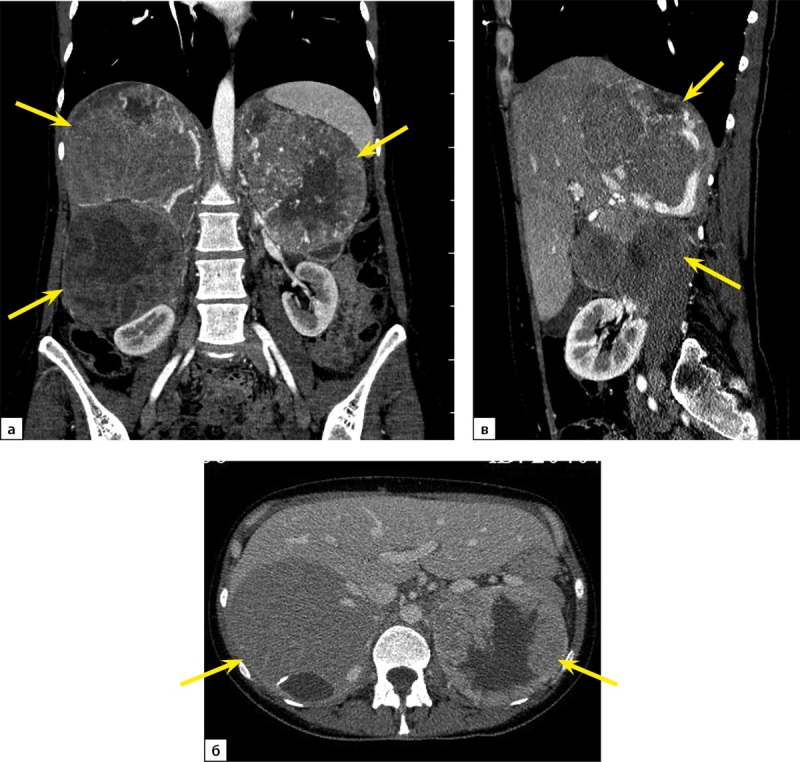

嗜铬细胞瘤(PHEO)目前被认为是恶性的,由于转移的潜力。最常见的家族性PHEO之一是多发性内分泌瘤变综合征(MEN) 2型。PHEO在MEN2综合征中的外显率高达50%。它可能是单侧或双侧,但转移发生极为罕见。在大多数MEN2综合征病例中,远处转移的来源是甲状腺髓样癌(MTC),这一事实使PHEO转移病例的鉴别诊断复杂化。本文报道了MEN2患者中PHEO转移至淋巴结、肺、肝、骨、脑的孤立病例。在现有文献中,我们发现了31例MEN2综合征转移性PHEO的描述。这些案例的可用数据以表格的形式呈现在本文中。我们报告了一名40岁女性MEN2A综合征(RET原癌基因p.Cys634Tyr突变),有两次手术治疗MTC的病史,每日伴有动脉高血压危像,伴有植物性症状,伴有巨大的双侧PHEO(右侧达200米,左侧达150毫米),同时伴有大转移(高达50毫米)进入耻骨并破坏。患者接受了几次手术:双侧肾上腺切除术,然后是双侧颈部翻修,切除右上、右下甲状旁腺,残余甲状腺组织,然后切除右耻骨肿瘤。

Pheochromocytoma (PHEO) currently is considered to be malignant due to metastatic potential. One of the most common familial forms of PHEO is multiple endocrine neoplasia syndrome (MEN) type 2. The penetrance of PHEO in MEN2 syndrome is up to 50% of cases. It may be one- or two-sided, but metastases occur extremely rare. The fact that in majority of cases of MEN2 syndrome the source of distant metastases is medullary thyroid carcinoma (MTC) complicates differential diagnosis in case of PHEO metastasis.Isolated cases of PHEO with metastases to the lymph nodes, lungs, liver, bones, brain in MEN2 patients were described. In the available literature, we have found a description of 31 cases of metastatic PHEO in MEN2 syndrome. The available data of those cases is presented as a table in the article.We present a description of a 40-year-old woman with MEN2A syndrome (mutation of the RET proto-oncogene p.Cys634Tyr), with a history of twice-performed surgical treatment of MTC, with daily crises of arterial hypertension accompanied by vegetative symptoms, with a giant bilateral PHEO (up to 200 m on the right and up to 150 mm on the left) with synchronous large metastasis (up to 50 mm) into the pubic bone with the destruction. The patient underwent several surgeries: bilateral adrenalectomy, then a bilateral revision of the neck, removal of the right upper and right lower parathyroid glands, residual thyroid tissue, then resection of the right pubic bone with a tumor.